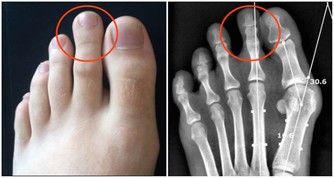

那麼,白頭髮的毛囊與黑頭髮的毛囊到底存不存在區別呢?記者來到了北京協和醫院利用專業儀器對頭髮進行觀察。

醫生說:「用肉眼或者是皮膚鏡看,白髮和黑髮沒有明顯的差別,只是毛髮的顏色有改變,具體兩個的差異是在毛囊的下部」。